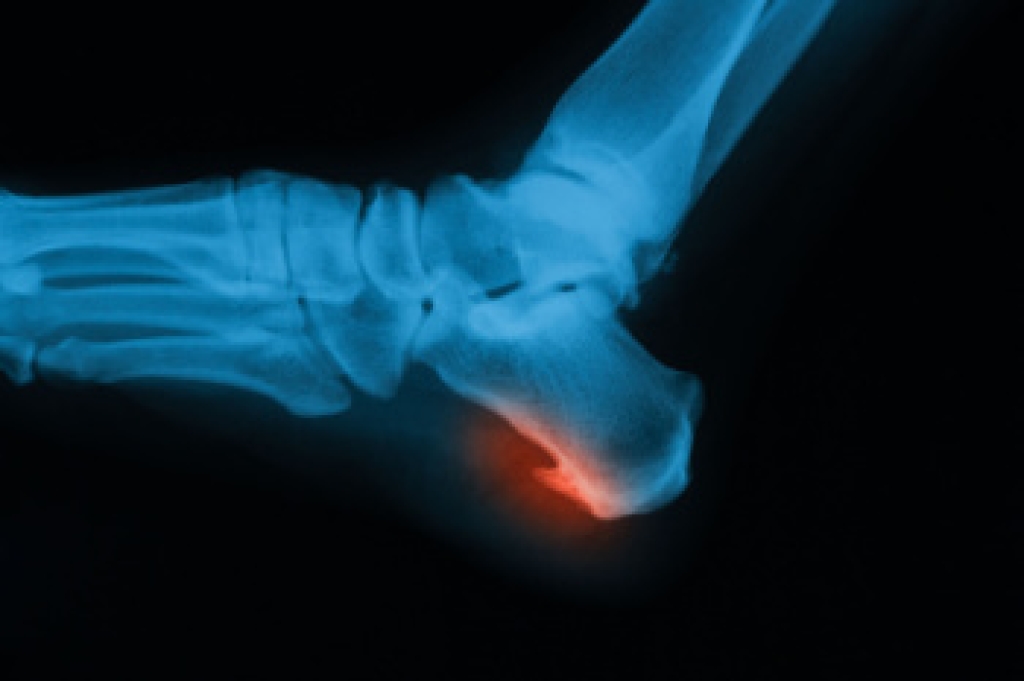

Heel spurs are formed by calcium deposits on the back of the foot where the heel is. This can also be caused by small fragments of bone breaking off one section of the foot, attaching onto the back of the foot. Heel spurs can also be bone growth on the back of the foot and may grow in the direction of the arch of the foot.

Heel spurs are bony growths that develop on the underside of the heel bone, often forming in response to long-term strain on foot muscles and ligaments. They can be caused by weakened muscles that fail to properly support the foot, joint stiffness that alters walking patterns, and repeated forced impact from walking or standing on hard floors. These factors place extra stress on the heel, leading to inflammation and pain. A podiatrist can diagnose heel spurs through examination and imaging, then recommend treatments like custom orthotics, stretching exercises, and supportive footwear. If heel pain is affecting your daily life, it is suggested that you consult a podiatrist who can accurately diagnose and treat heel spurs.